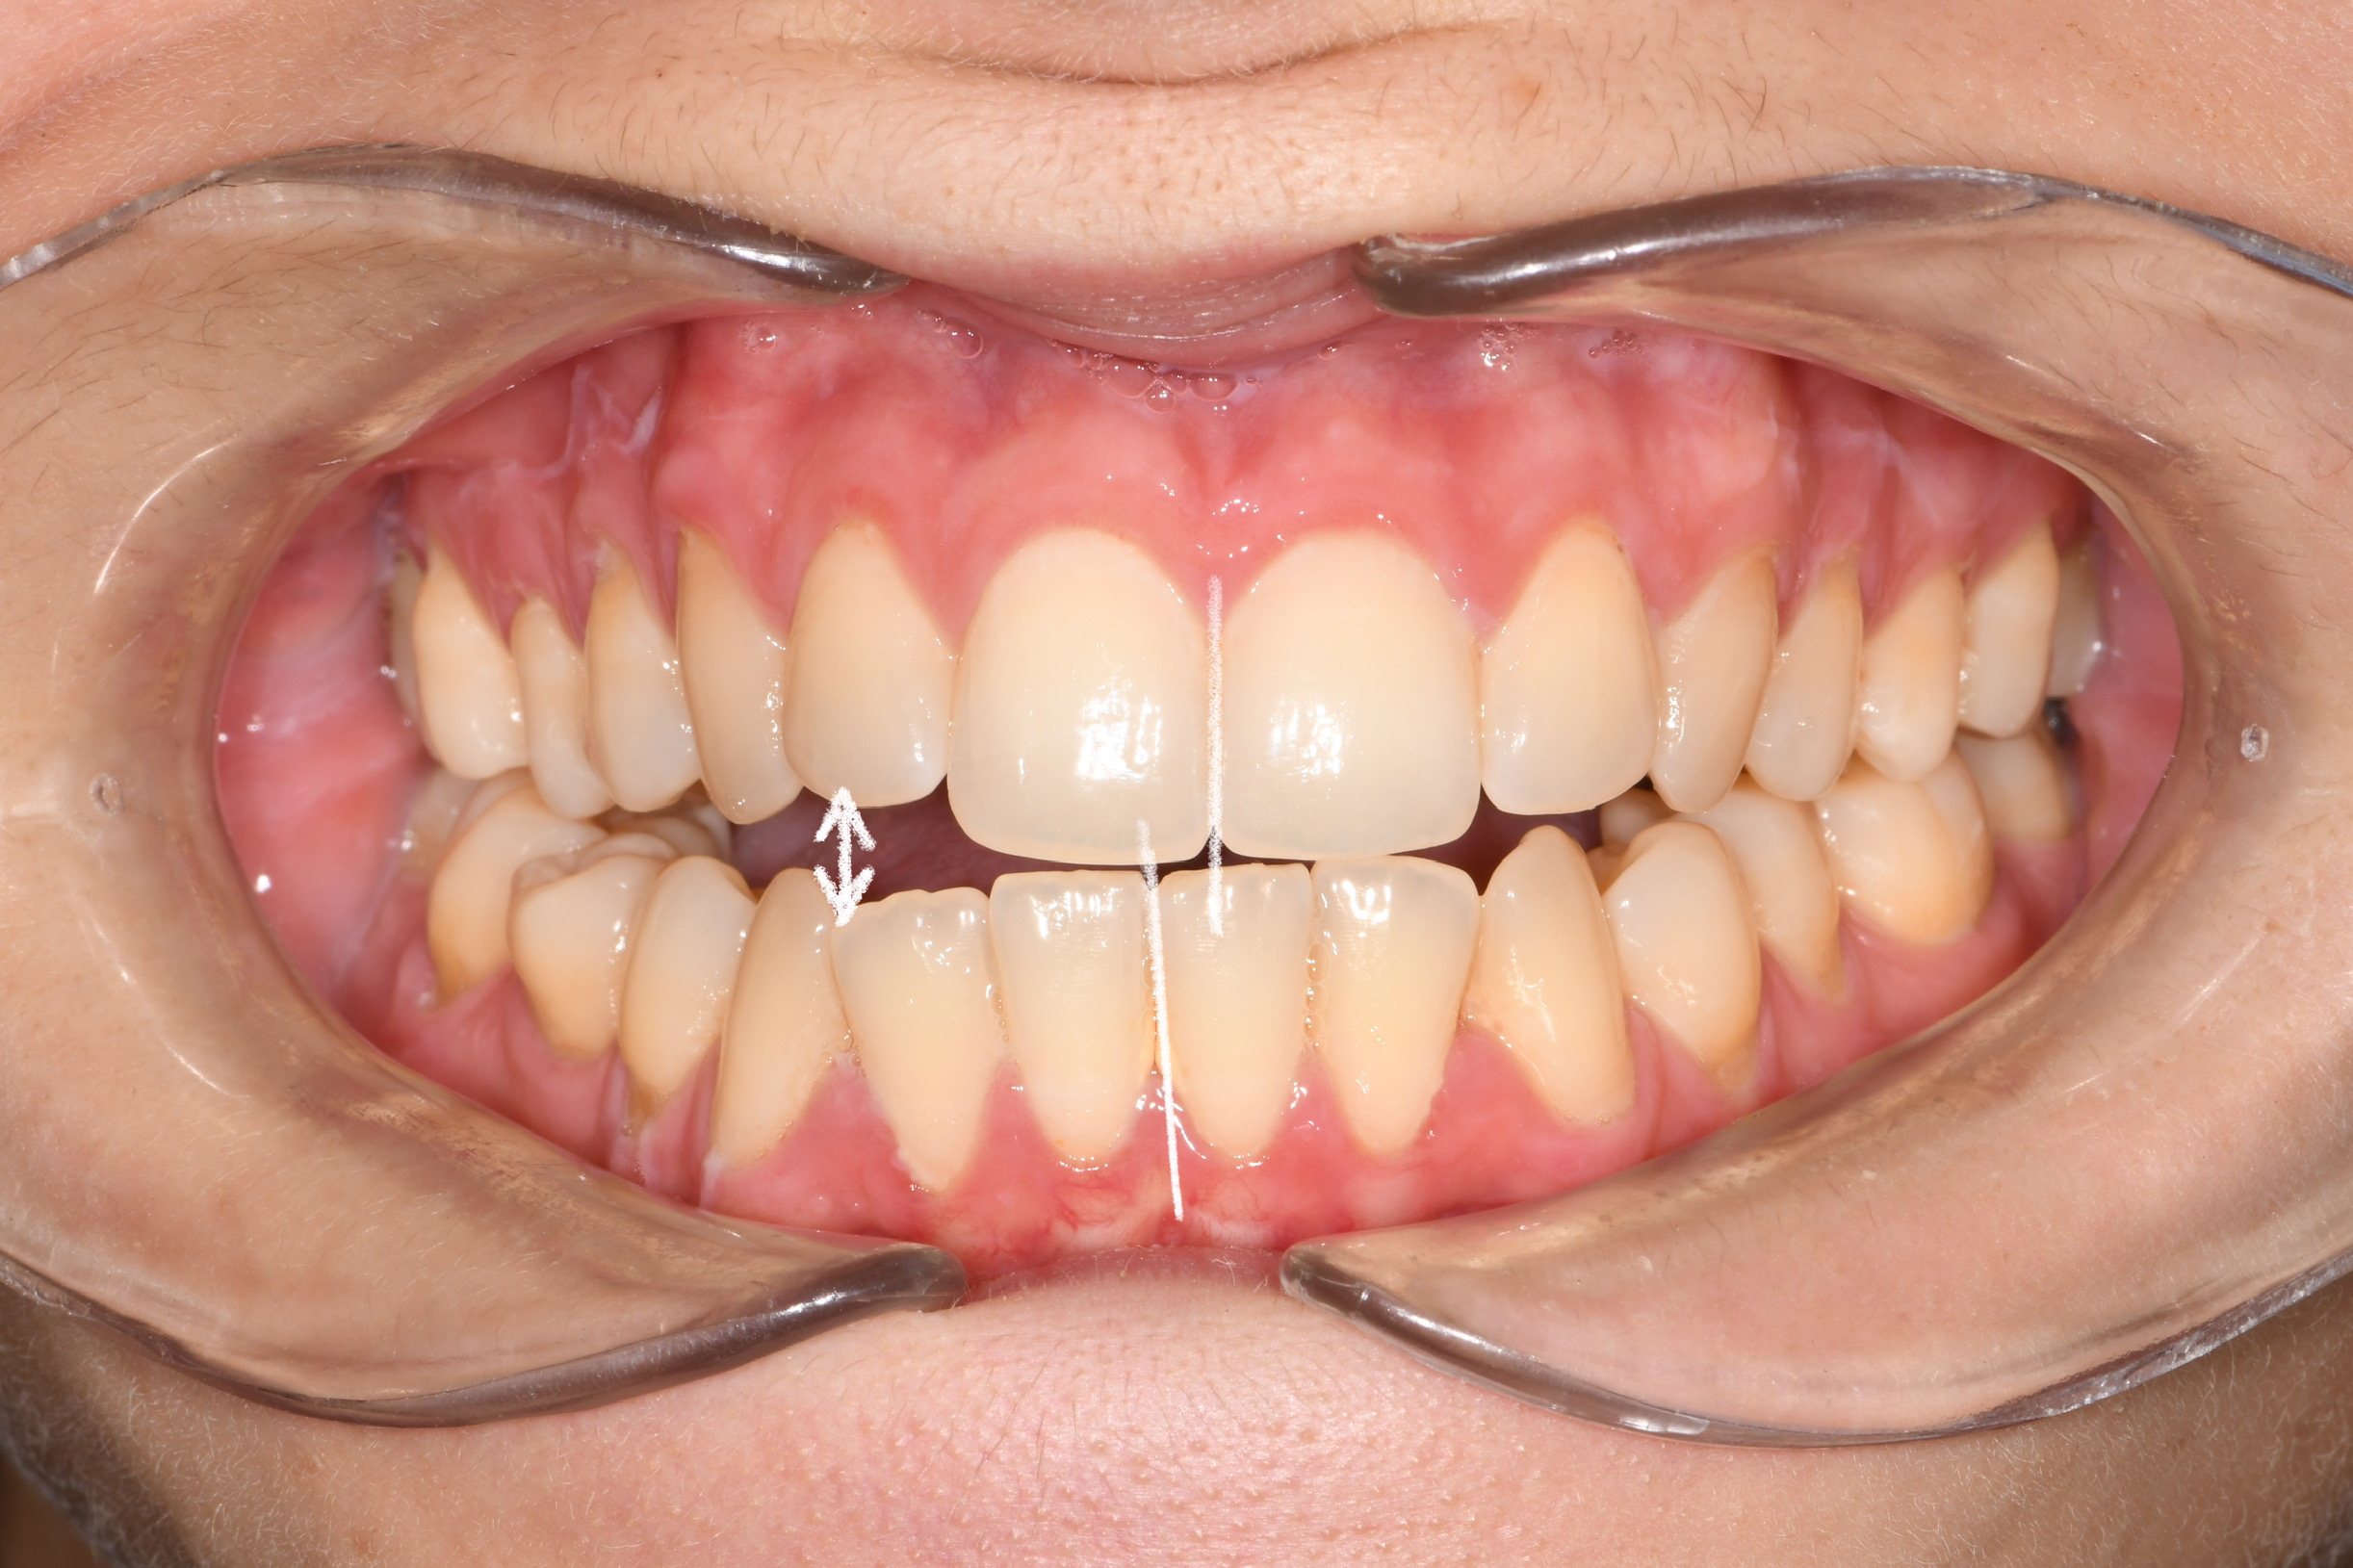

Az elmúlt évekből rengeteg szakmai referenciát tudnánk bemutatni, amelyek különböző fogszabályozási problémákat oldottak meg. Válogatva a több száz esetből, ezen az oldalon olyan képeket, információkat igyekeztünk bemutatni, amelyeknek a segítségével a jövőbeni pácienseinknek azt tudjuk üzenni: A Te fogsorod is lehet gyönyörű!

(Képeket a Pácienseink külön írásos beleegyezésével mutatjuk be!)